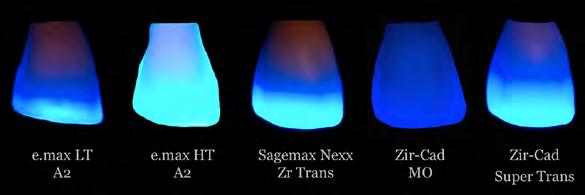

Diversos estudios han demostrado que el cepillo se contamina con diferentes tipos de bacterias, virus u otros microorganismos después de su uso. Estos microorganismos son capaces de alojarse en la superficie microtexturizada de las cerdas (Figura 1).

Debido a que el implante tenía una excelente posición tridimensional y una buena estabilidad primaria, se colocó una prótesis provisional cementada con una conformación perfecta del perfil de emergencia (Figura 11-16) y fuera de oclusión con el diente antagonista. (Figura 17) Durante la fase de provisionalización, se colocó un punto de sutura colchonero horizontal para mantener el tejido blando y evitar cualquier posible recesión. (Figura 18) 3 meses después, observamos una gran banda de tejido queratinizado con un gran resultado estético. (Figura 19) Se tomó una impresión a cucharilla cerrada y se colocó un análogo sobre la impresión. (Figura 20 y 21) El implante Straumann® PURE monotype debe restaurarse con prótesis totalmente cerámicas, por lo que decidimos hacer 5 núcleos de cerámica diferentes para evaluar la translucidez de los mismos:

21 1. e.max LT A2, 2. e. max HT A2, 3. Sagemax NexxZr Trans, 4. ZirCAD MO, 5. ZirCAD Super Trans (Figura 22).

Si la translucidez es necesaria para la restauración, la solución más adecuada es una cofia e.max HT (disilicato de litio), pero si la translucidez debía ser bloqueada, la cofia ZirCAD (zirconia) era la solución más adecuada. (Figura 23) Para optimizar el efecto visual de la translucidez de las cofias, creamos un análogo de zirconia (Figura 24 y 25) para probar la translucidez de las cofias cerámicas y evaluar cómo se comportarían cuando se cementen en su lugar.